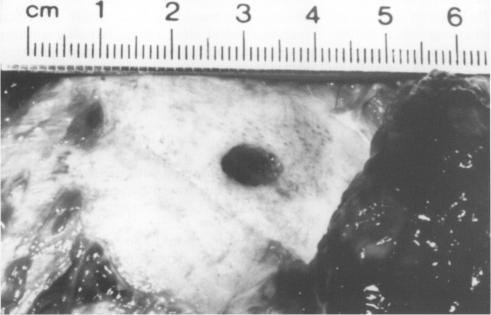

Five cases of fatal airgun injury were identified by forensic pathologists and histopathologists. The circumstances surrounding the case, radiological examination, and pathological findings are described. The weapon characteristics are also reported.

Three of the victims were adult men, one was a 16 year old boy, and one an eight year old child. Four of the airguns were .22 air rifles, the other a .177 air rifle. Two committed suicide, one person shooting himself in the head, the other in the chest. In both cases the guns were fired at contact range. Three of the cases were classified as accidents: in two the pellet penetrated into the head and in one the chest.

方法

受害者中3人为成年男性,1人为16岁男孩,1人为8岁儿童。气枪中有4把是.22气步枪,另一把是.177气步枪。2人自杀,一人朝头部开枪,另一人朝胸部开枪。两起案件中枪都是在接触距离发射的。3起案件被归类为意外:2起中弹丸射入头部,1起射入胸部。